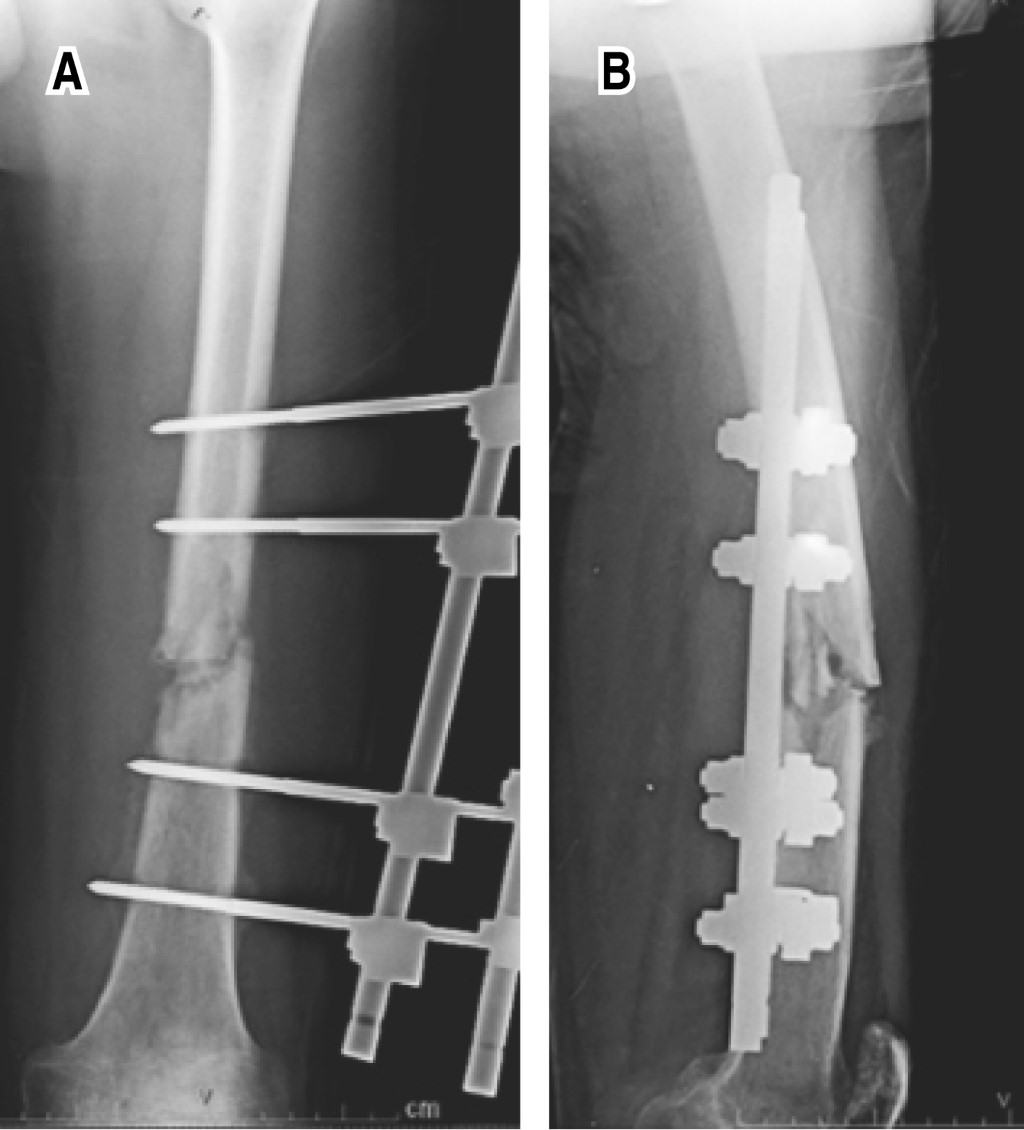

Por esta razón se realiza procedimiento quirúrgico que inicia con retiro de fijador externo y, mediante un abordaje lateral para fémur, se localiza el sitio de la pseudoartrosis, el cual se reseca con sierra oscilante hasta encontrarse tejido óseo viable, quedando un defecto óseo de aproximadamente 5 cm. Posteriormente, se procede a realizar incisión paratendón rotuliano, se localiza punto de entrada para clavo centromedular retrógrado, se realiza rimado del canal medular y se coloca clavo centromedular retrógrado de fémur izquierdo bloqueado con dos pernos proximales y tres distales al foco de pseudoartrosis 11 × 360 mm. De forma simultánea se extrae injerto óseo autólogo de cresta iliaca de alrededor de 4.5 cm, el cual se prepara en pequeños fragmentos de 3 mm aproximadamente. Por último, se realiza aspirado de médula ósea de cresta iliaca mediante aguja Jamshidi 11 G × 10 cm, se obtienen dos jeringas de 10 ml, se procede a combinar el injerto óseo autólogo con el aspirado de médula ósea sobre un riñón, el cual se utiliza para rellenar el defecto óseo y emplea las esponjas de gelatina (Gelfoam Pfizer) como andamio para dar contención del injerto, al colocarse cuatro porciones de 8 × 6.5 cm de forma circunferencial al hueso que conecta así los bordes del trazo de fractura (Figura 2).

Se lleva a cabo procedimiento quirúrgico, que inicia con retiro de placa en fémur izquierdo mediante abordaje lateral, se localiza foco de pseudoartrosis y se realiza resección de aproximadamente 3 cm con sierra oscilante, hasta encontrarse tejido óseo viable. Posteriormente se realiza incisión paratendón rotuliano, se localiza punto de entrada para clavo centromedular retrógrado, se rima canal medular y se coloca clavo centromedular retrógrado de fémur bloqueado con dos pernos proximales y dos distales al foco de la pseudoartrosis 11 × 360 mm. De forma simultánea se toma injerto autólogo de cresta iliaca de 3 cm aproximadamente, se realiza aspirado de médula ósea con aguja Jamshidi 11 G × 10 cm, se hace mezcla de igual forma que con nuestro primer caso y se rellena el defecto óseo; finalmente, se colocan cuatro porciones de esponjas de gelatina absorbible (Gelfoam) de 8 × 6.5 cm con la misma distribución para dar contención a nuestro injerto (Figura 2).

Figura 2